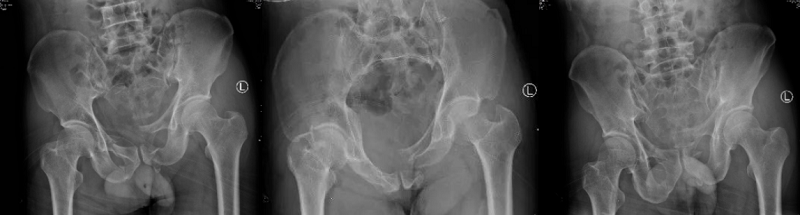

術前X線片